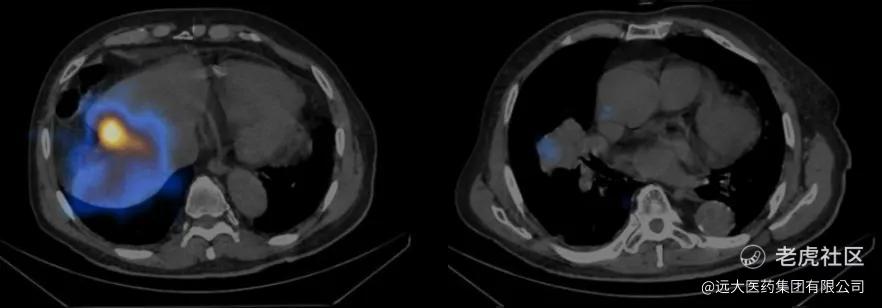

如图1~图6所示,肝及肺内蓝黄色为钇-90沉积区域,亮度越高,表明吸收剂量越大,随着治疗后时间的延长可以看到颜色的亮度逐渐减弱。

(左:图3 SIRT后肝扫描(24h);右:图4 SIRT后肺扫描(24h))